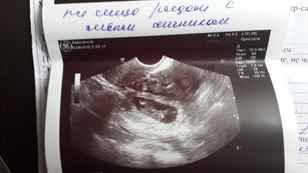

Видны ли признаки внематочной беременности на УЗИ?

УЗИ не всегда является информативным методом, так как на ранних сроках заметить плодное яйцо бывает невозможно и часто могут спутать сгустки крови или слизи в матке с маточной беременностью. Случалось наблюдать, что у женщины одновременно развивается две беременности, одна из которых маточная, которую и видит аппарат УЗИ, другая — внематочная. Если все же УЗИ тоже не подтверждает внематочную беременность, а подозрения на нее есть, то женщину могут положить в больницу для проведения соответствующей диагностики и лечения.